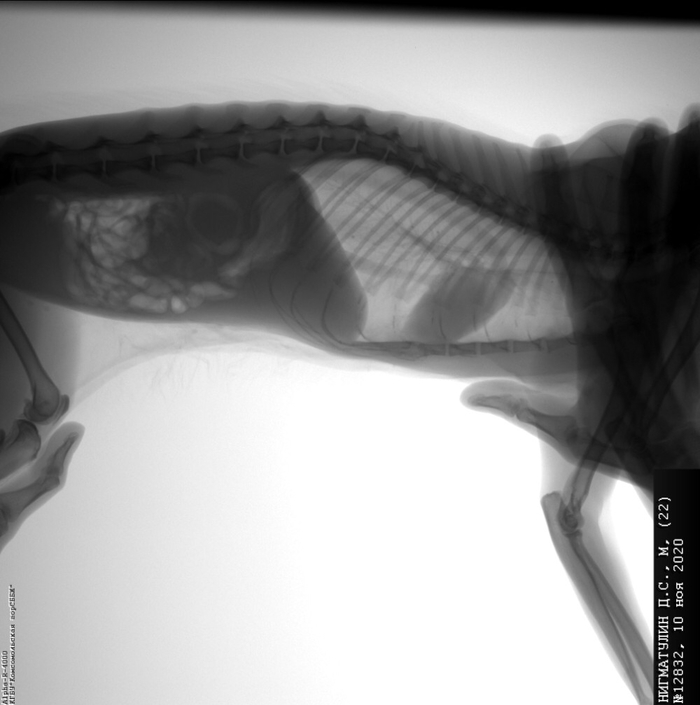

Вот она, круглая, чуть левее середины, темное, круглое пятно со светлой окантовкой. Опухоль в печени, приросшая ко всему, метастазы в легкие (нет там метастаз), неоперабельна. Злокачественная (это без гистологии, чисто по снимку, за*бись). Даже если была бы операбельная, в таком состоянии может не выйти из наркоза.

Рентген делала другой врач. Посмотрела прошлый снимок, сказала, что никаких метастаз в легкие нет, это возрастное (кольцевание? вроде так сказала), сердце опущено, тоже возрастное. Также сказал и мой знакомый выпускник меда, метастаз не видит.